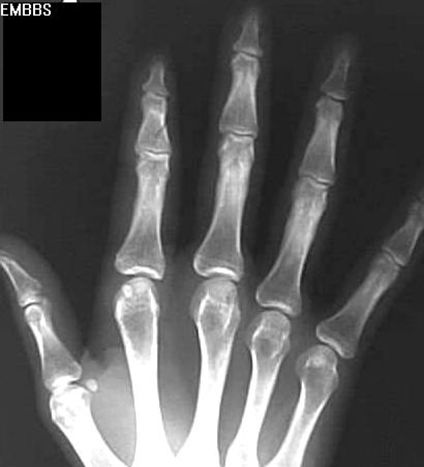

指骨骨折

疼痛科怎么理疗疼痛科医生、康复理疗科医生、针刀针灸医生应掌握的常见骨科疾病X光片_https://www.jmylbn.com_新闻资讯_第29张